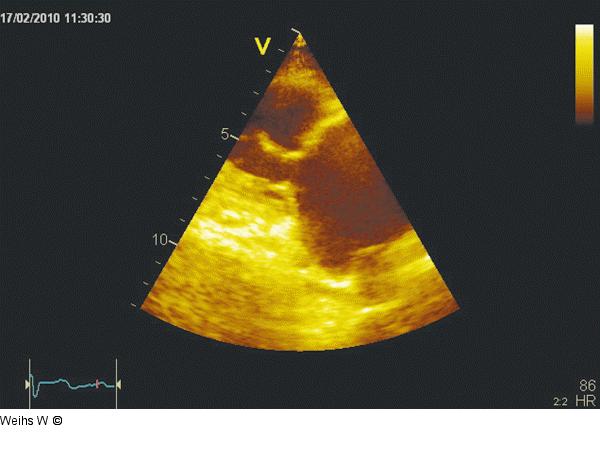

Abbildung 2: Parasternaler Längsschnitt Parasternaler Längsschnitt des rechten Ventrikels mit Darstellung des anterioren und posterioren Trikuspidalsegels. Beide Segel sind geschrumpft und starr mit bereits zweidimensional erkennbarer fehlender Koaptation der Segel. |

Parasternaler Längsschnitt des rechten Ventrikels mit Darstellung des anterioren und posterioren Trikuspidalsegels. Beide Segel sind geschrumpft und starr mit bereits zweidimensional erkennbarer fehlender Koaptation der Segel. |